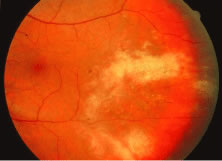

The ARN patient typically presents with progressive visual blurring in one or both eyes occurring over several weeks. These patients often are initially treated with corticosteroids, antitoxoplasmosis drugs, and other medications before arriving at the correct diagnosis. Examination reveals a prominent anterior uveitis that may be granulomatous or nongranulomatous (Fig. 1). Inflammatory signs may be prominent and cause severe pain (Fig. 2). The uveitis may be diffuse and so severe that it causes proptosis. These signs, and the diffuse vitreitis that makes the view of the retina difficult, may contribute to the high degree of delayed and/or misdiagnosis that occurs in the early stages of the disease. Significant vitreous cellular infiltration is seen in the presence of retinitis that is manifest by opacification of the retina, often most prominently in the periphery. Posterior pole involvement may include retinitis, as well as inflammation of the optic nerve head. Optic neuropathy might be the first sign of ARN with subsequent development of other retinal manifestations.8 Ultrasonography and computed tomography (CT) might be helpful in cases of ARN associated with optic nerve edema revealing enlargement of the optic nerve sheath.9 Even in ARN patients who are not immunocompromised and who have no clinical evidence of encephalitis, magnetic resonance imaging of selected cases has shown lesions of the lateral geniculate, optic tracts, and chiasma, which suggests that the virus spreads through the central nervous system (CNS) by axoplasmic transport from the retinal ganglion cells.10 A secondary retinal vasculitis is common, often accompanied by a mild number of retinal hemorrhages. Days to weeks after onset of the infection, the discrete peripheral lesions typically coalesce into a white or yellow ring of infected retina, and the associated vasculature is obliterated (Fig. 3). Necrotic retina desquamates into the vitreous resulting in vitreous sheets.3,6 Eventually, most untreated eyes can be expected to develop retinal detachment resulting from development of multiple full-thickness retinal breaks accompanied by traction or exudation.11 Giant retinal pigment epithelial tears have also been reported.12